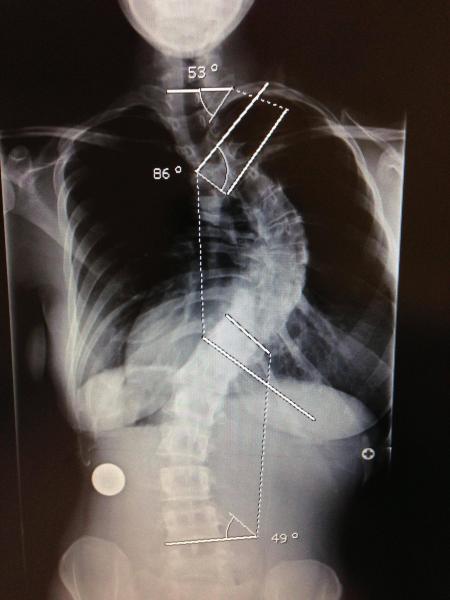

Operaţia este recomandată pentru cazuri foarte grave, când coloana este curbată la peste 50 de grade.